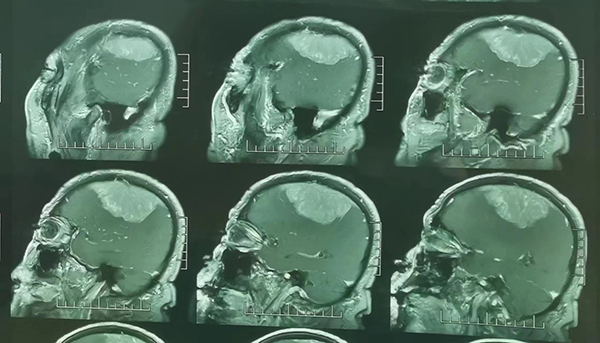

苗發(fā)安副主任醫(yī)師接診后,安排劉老先生住院進(jìn)一步完善了相關(guān)檢查,結(jié)果發(fā)現(xiàn)劉老先生顱內(nèi)長(zhǎng)了一個(gè)大小約10cm*8cm大小的腦膜瘤。腫瘤不僅僅體積大,位置也不好,壓在了右腦的運(yùn)動(dòng)區(qū),術(shù)后很可能會(huì)出現(xiàn)左側(cè)肢體偏癱等并發(fā)癥。診斷明確后顱底腫瘤外科主任范月超教授、梁君主任醫(yī)師組織科室進(jìn)行了手術(shù)方案的討論,結(jié)合患者年齡、癥狀,腫瘤大小、位置等,制定了周密的術(shù)前準(zhǔn)備和手術(shù)方案。

11月15日,由苗發(fā)安副主任醫(yī)師主刀實(shí)施手術(shù)。在麻醉科手術(shù)室同事的全力配合下,手術(shù)團(tuán)隊(duì)克服了腫瘤巨大、開顱出血、腫瘤和骨瓣黏連融合、腫瘤和正常腦組織及運(yùn)動(dòng)區(qū)腦皮層黏連等難題,歷時(shí)5個(gè)小時(shí),將腫瘤分塊全切除。術(shù)后患者經(jīng)過(guò)相關(guān)治療和護(hù)理,恢復(fù)良好,左側(cè)肢體運(yùn)動(dòng)幾乎不受影響,術(shù)后當(dāng)日意識(shí)恢復(fù)清醒,5天后即下床活動(dòng),11月29日順利康復(fù)出院。